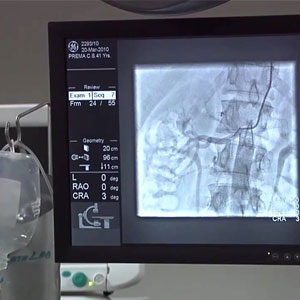

Angiogram is a special X-ray to take pictures of blood vessels. Angioplasty is done to restore blood flow through the vessel using a thin tube. The best cardiologist in Guntur specializes in diagnosing and treating diseases of the cardiovascular system. The heart specialist at heart hospitals in Guntur will carry out Emergency heart care treatment and they may do some procedures, such as heart catheterizations, angioplasty, or inserting a pacemaker, etc. Narayana Hospitals is known as the best cardiology hospital in Guntur and also for the best treatment for heart failure and also heart-related problems. we are also specialized for the best open heart surgery, bypass surgery and all cardiac problems.